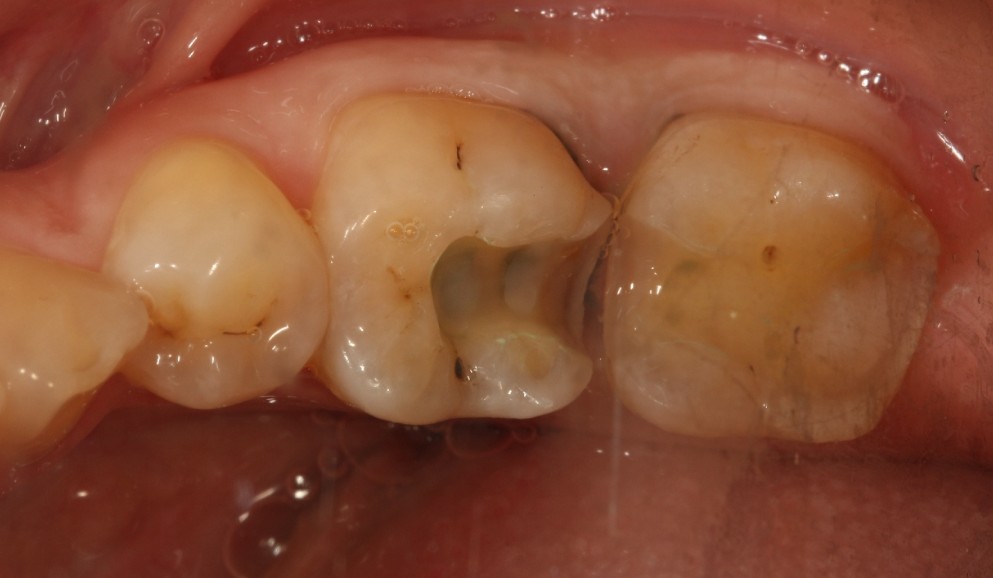

口腔检查时,会经常遇到以前补的银汞合金边缘变色,探有卡顿,形成了继发龋坏,建议重新充填或者瓷嵌体修复;瓷嵌体修复技术,可以非常好的恢复牙体形态和非常密合的边缘,色泽也非常逼真;我们采用CEREC(德国瓷睿刻)椅旁加工技术,达到最佳修复效果!